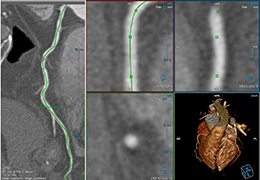

ANYTHINK 经导管主动脉瓣膜置换术分析系统